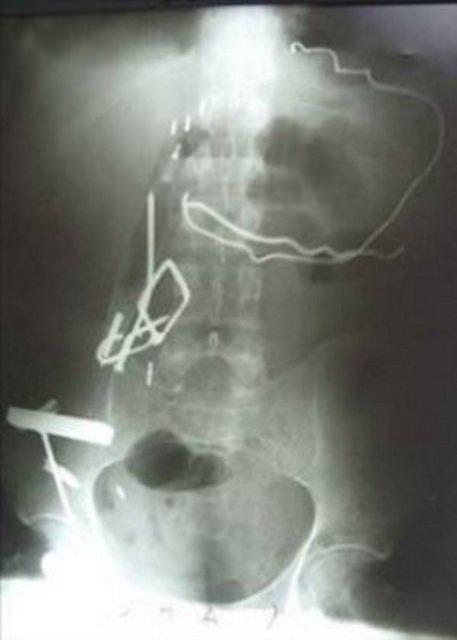

İran'da, korkusunu bastırmak ve sıkıntılarından kurtulmak için madeni nesneleri yiyen genç kızın karnından ameliyatla yarım kilogram ağırlığında metal parçalar çıkarıldı.